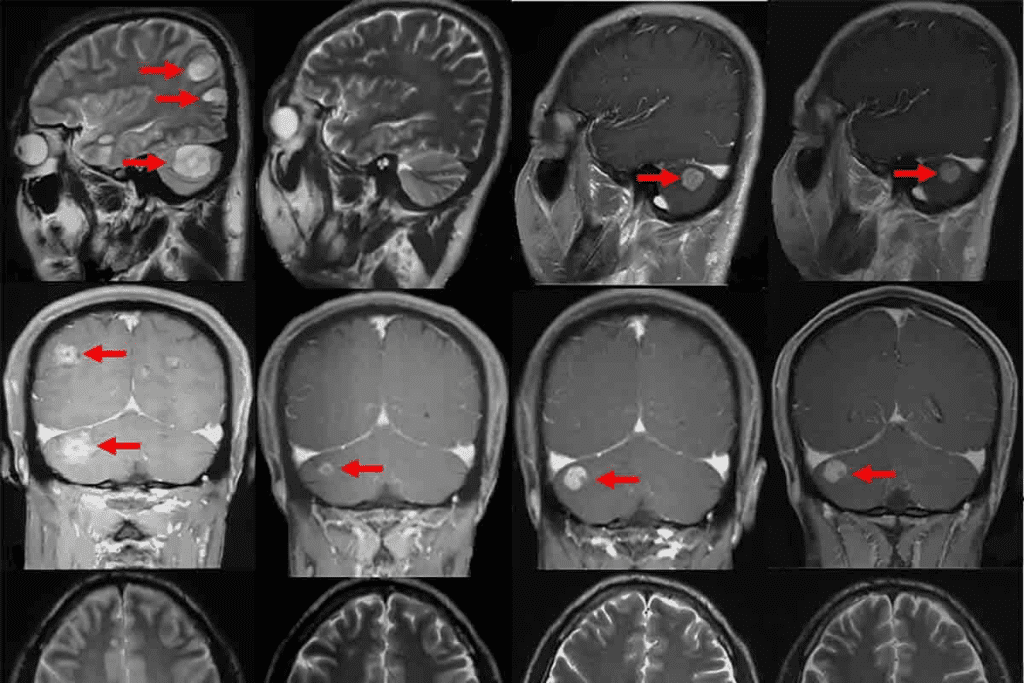

Brain Tumor Imaging

MRI is great for brain tumors because it can tell soft tissues apart. It shows the tumor’s size, location, and type, which helps doctors choose the best treatment. “MRI is vital in neuro-oncology,” experts say, “for accurate diagnosis and planning.”

Liver and Abdominal Cancer Visualization

MRI helps see liver and abdominal cancers, giving detailed images for diagnosis and staging. It’s great for checking major blood vessels and whether the tumor can be removed.